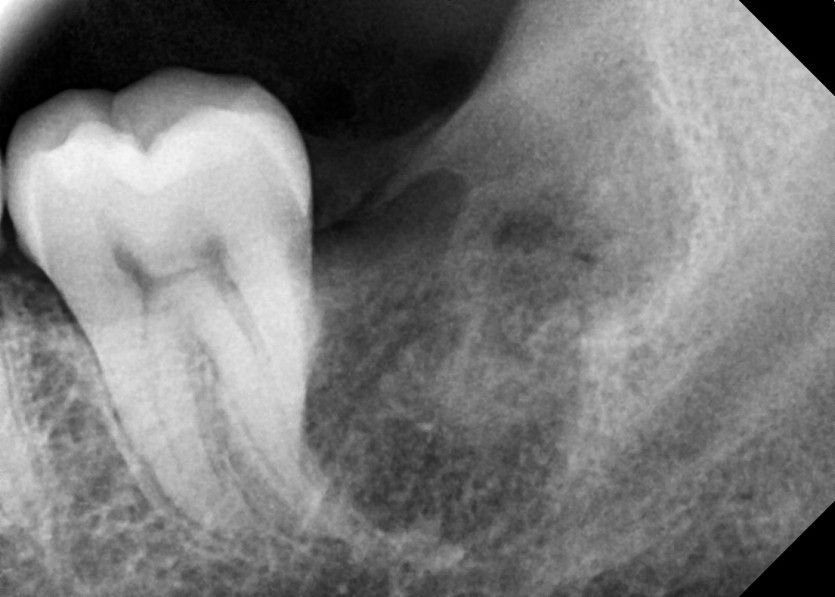

#38 사랑니 발치

구강 외과 전문의가 당일 발치했습니다.